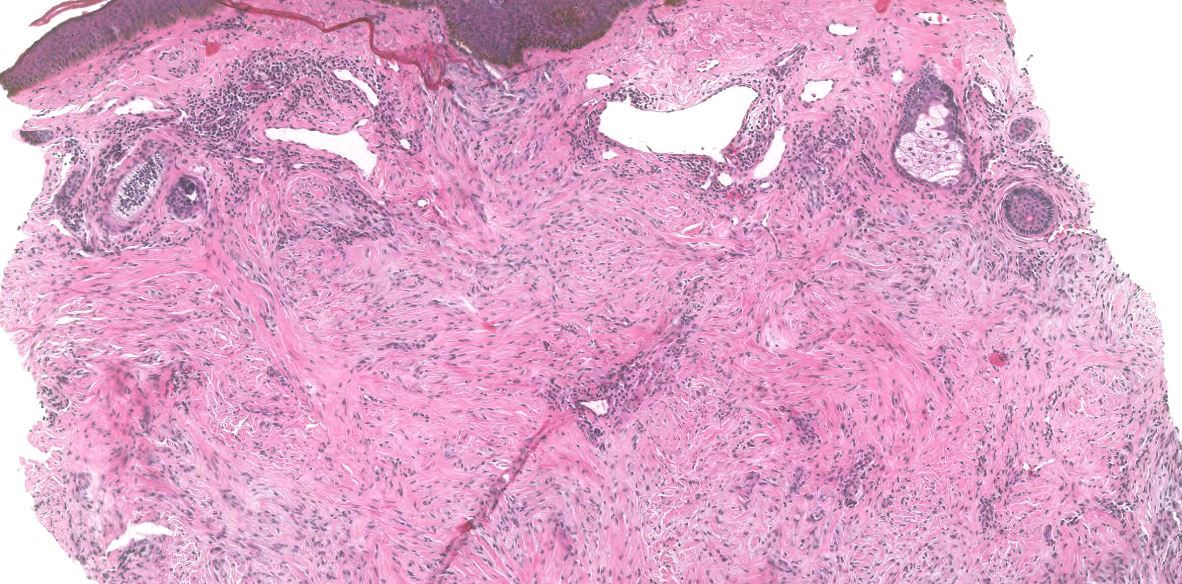

Dermatofibroma